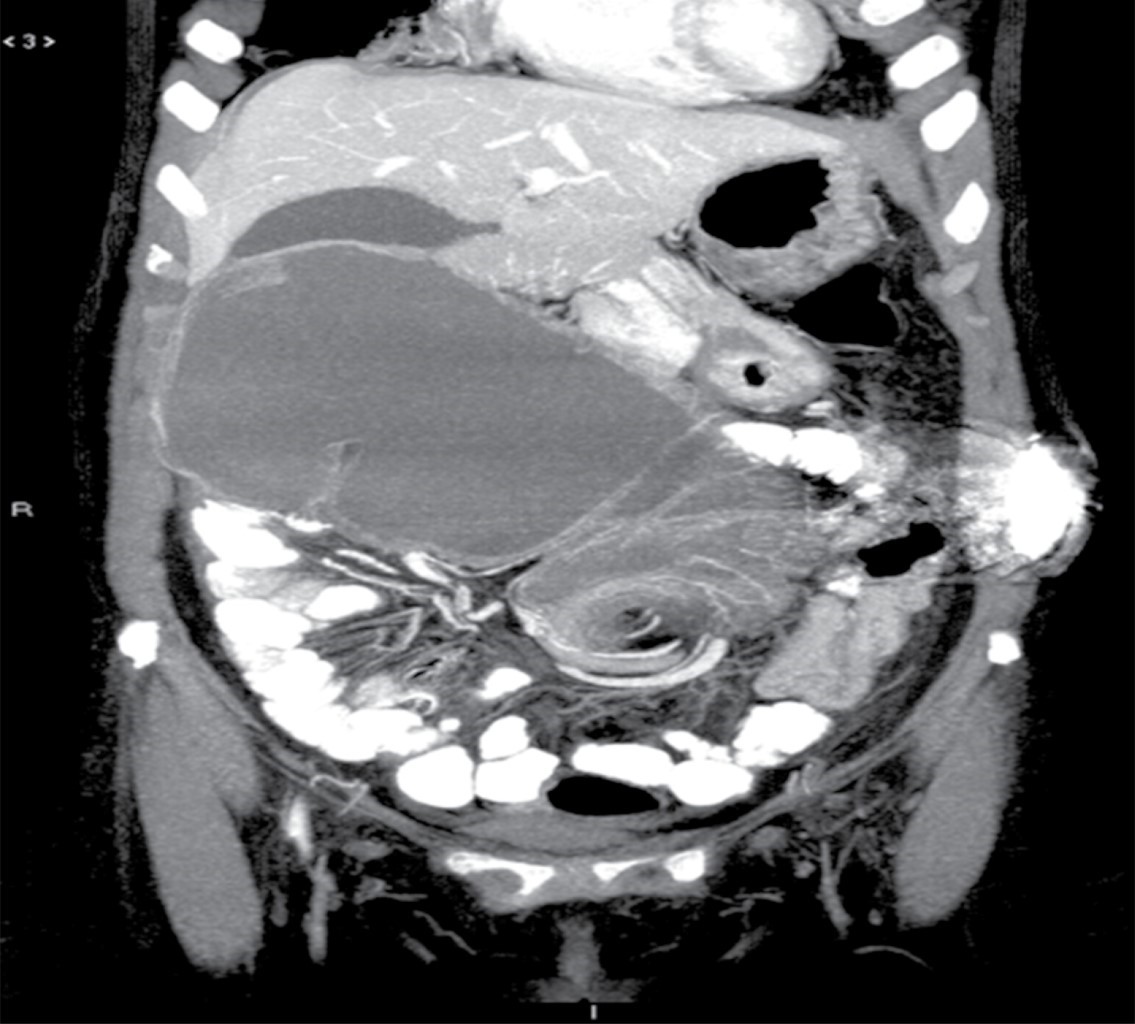

Se solicitaron estudios de laboratorio, los cuales reportaron 12,000 leucocitos por milímetro cúbico, siete bandas y niveles de lactato sérico de 2.8 mmol/l. Posteriormente se realizó una tomografía de abdomen con doble contraste, encontrando importante dilatación cecal, dilatación de colon ascendente y de la porción proximal de colon transverso, junto con una zona de transición hacia tercio distal, localizado en fosa iliaca izquierda. De igual manera, se encuentra hernia de pared abdominal supraumbilical en línea media con escaso tejido graso y epiplón (Figuras 1, 2, 3 y 4).

Figura 3